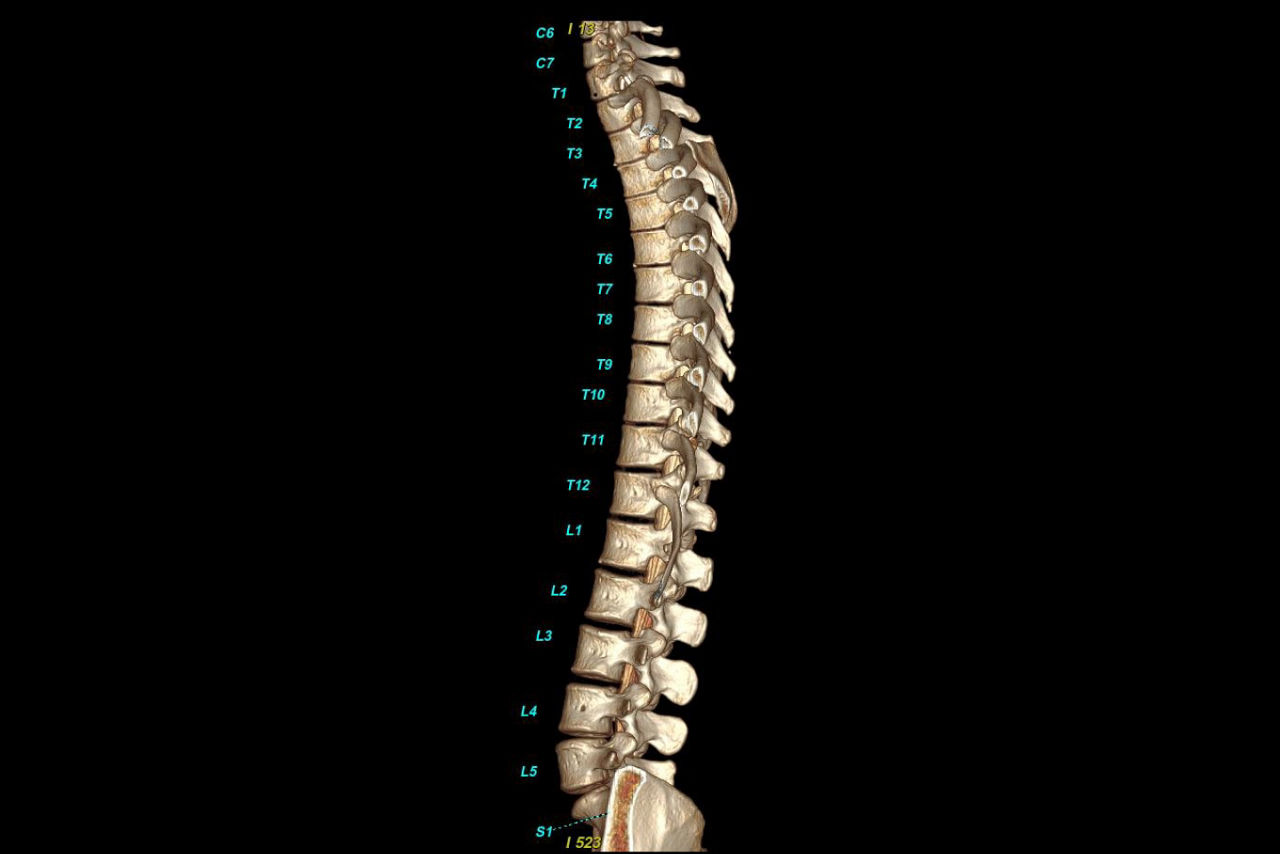

Bone VCAR

Spine assessment with deep-learning based CT application.

>90% labeling accuracy based on Deep learning algorithm trained on global datasets acquired with a broad range of acquisition parameters.

• Automated spine labeling

• Load multiple series and vertebrae labeling will propagate to the different volumes

• Works on full spine acquisitions as well as limited acquisitions containing segments of the spine